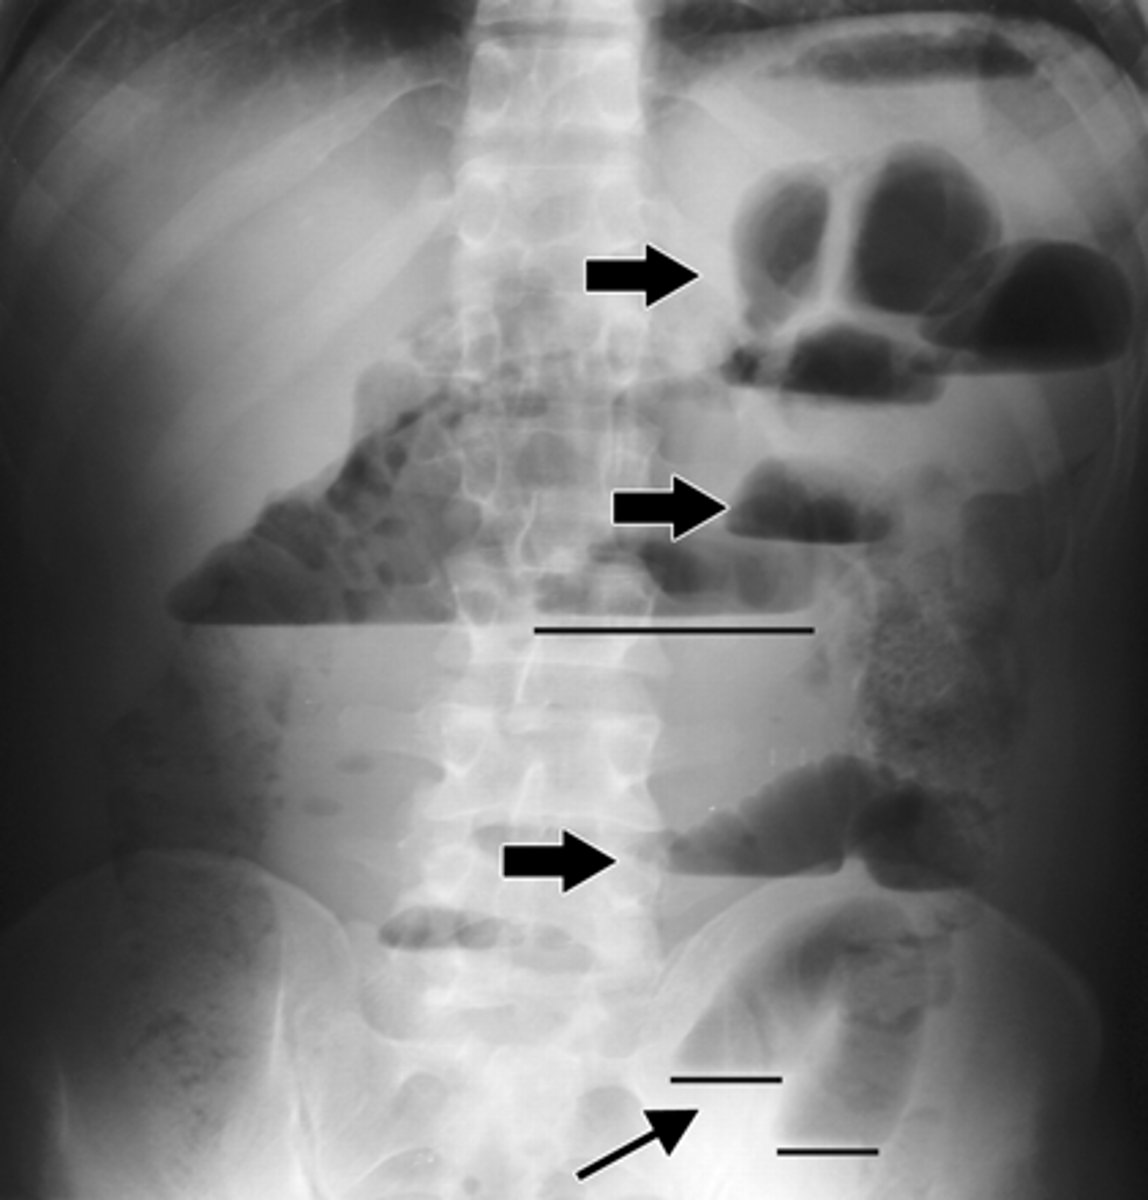

Where do you measure for abdominal radiographs?

last rib/diaphragm to the end of the pelvis.